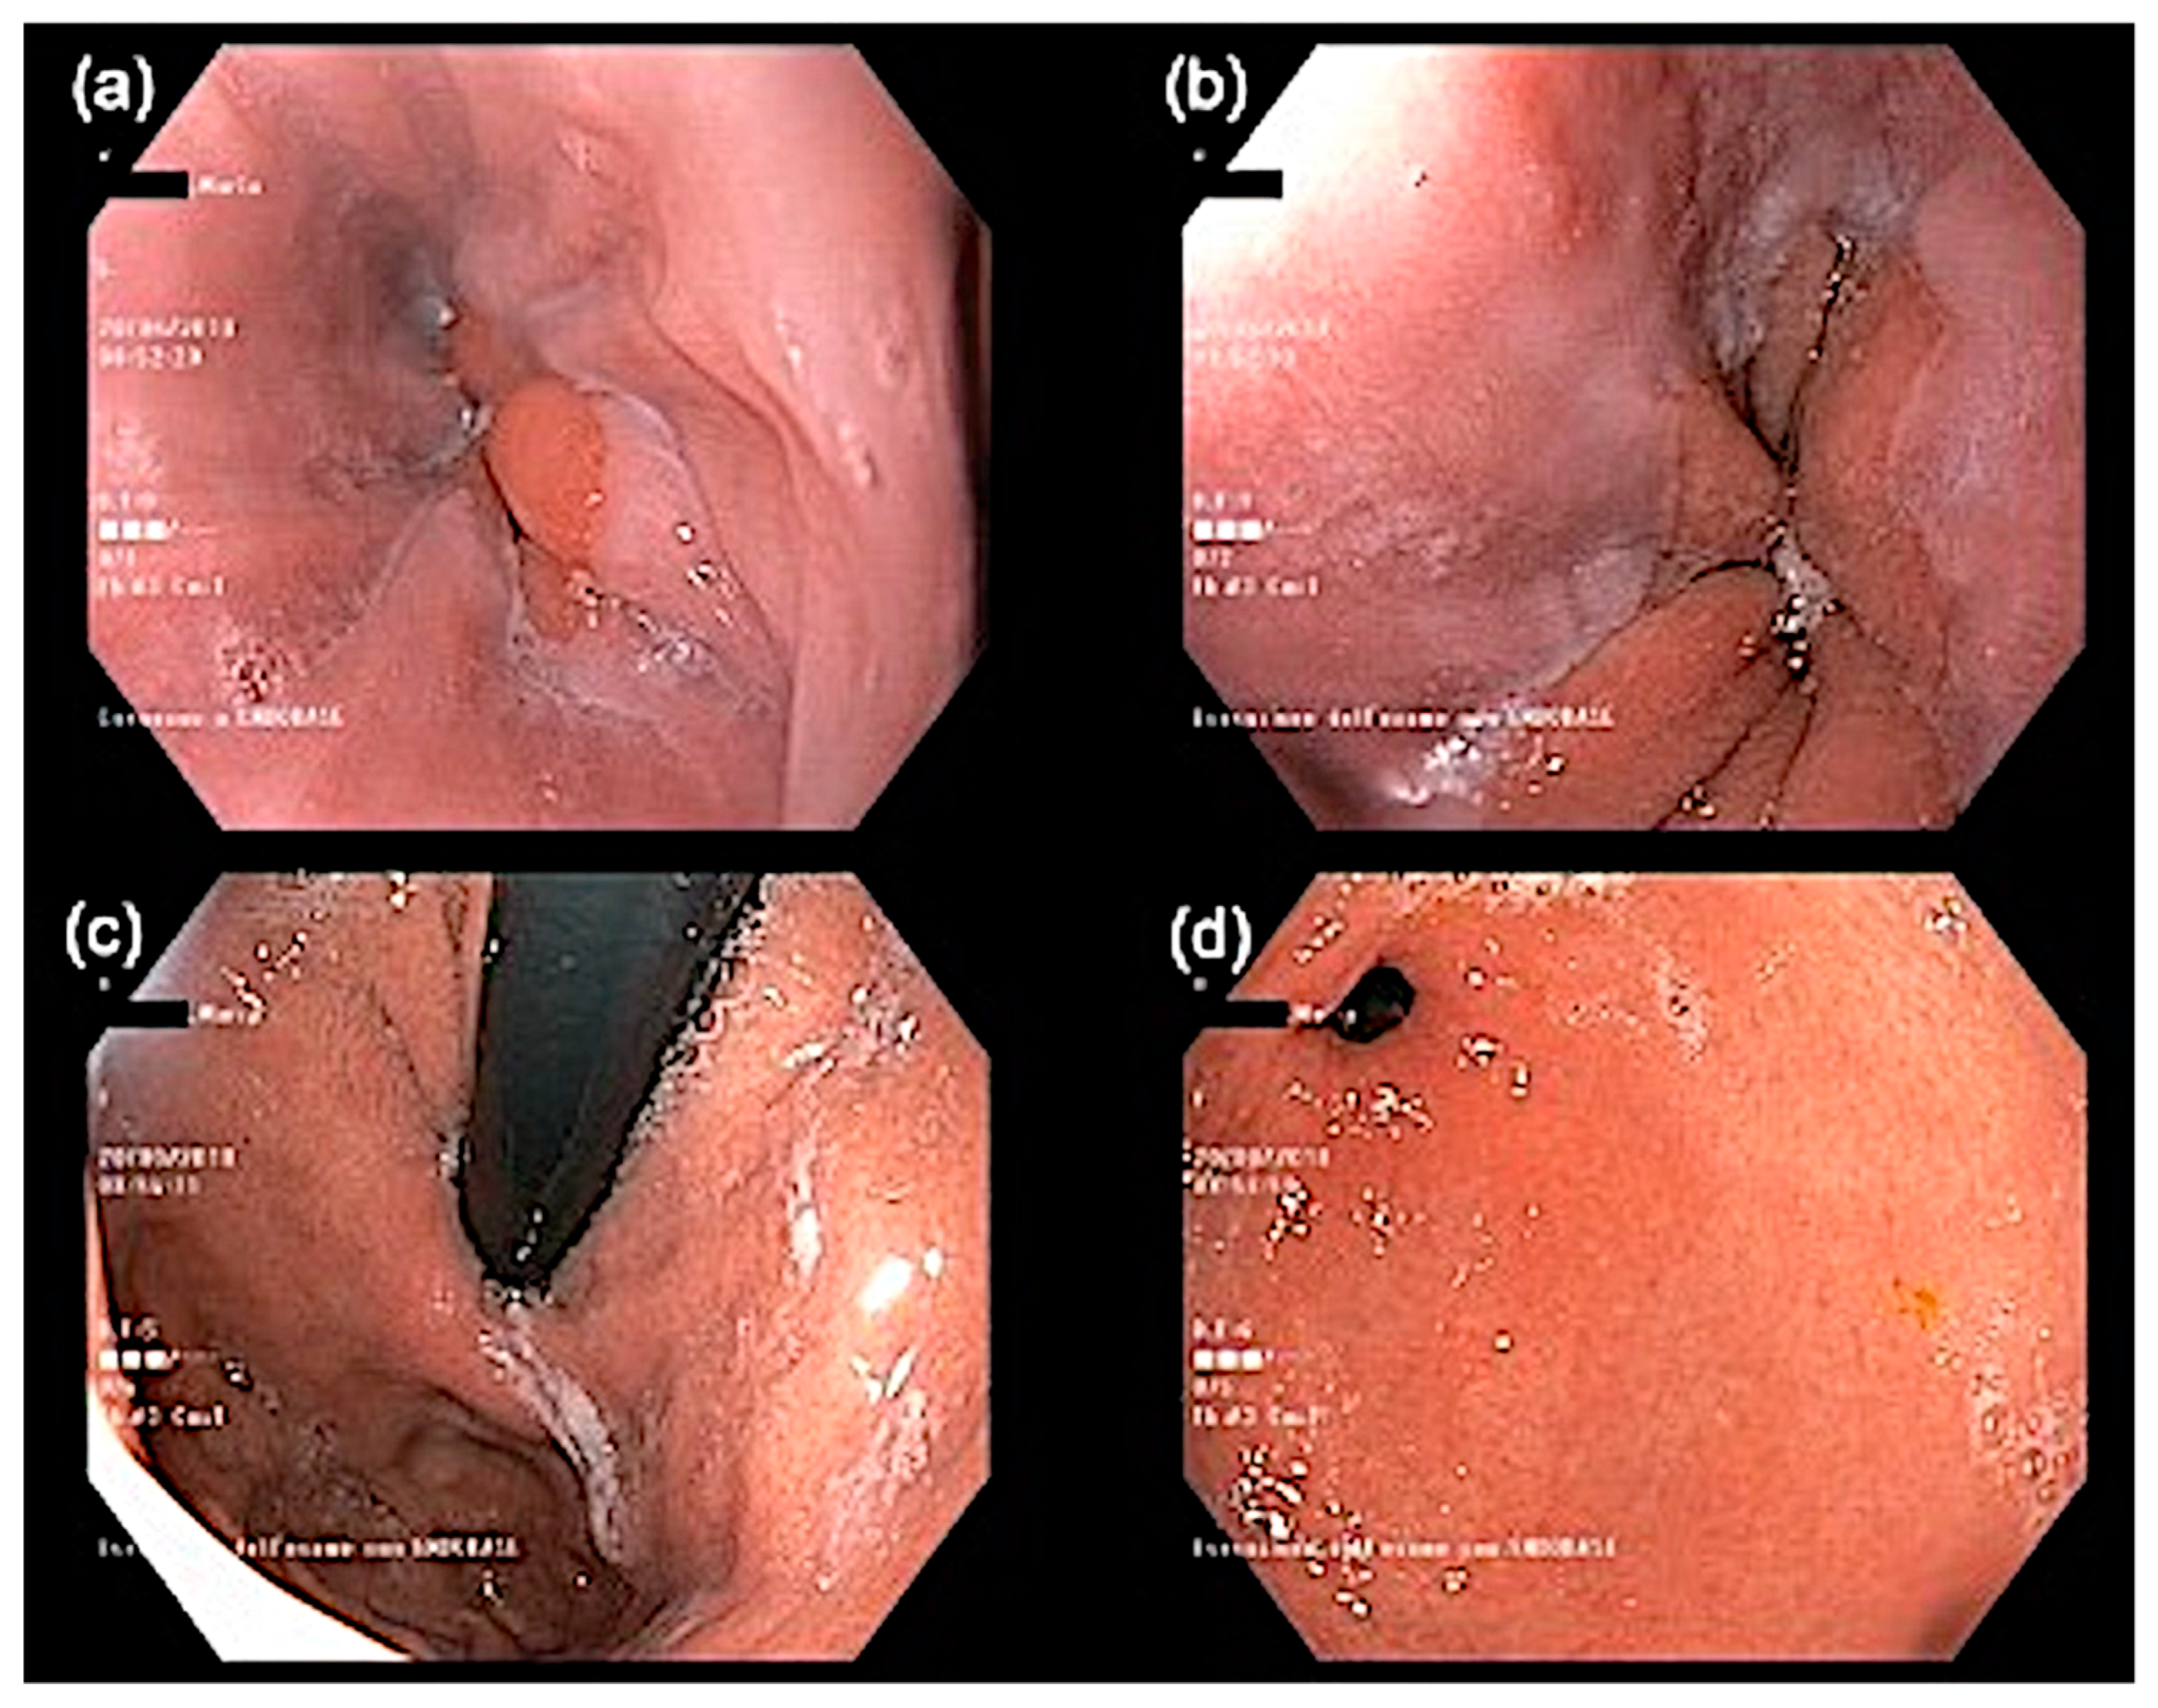

| Upper GI endoscopy | Mild esophagitis | - |

| GI histology | No eosinophilic infiltrate | |